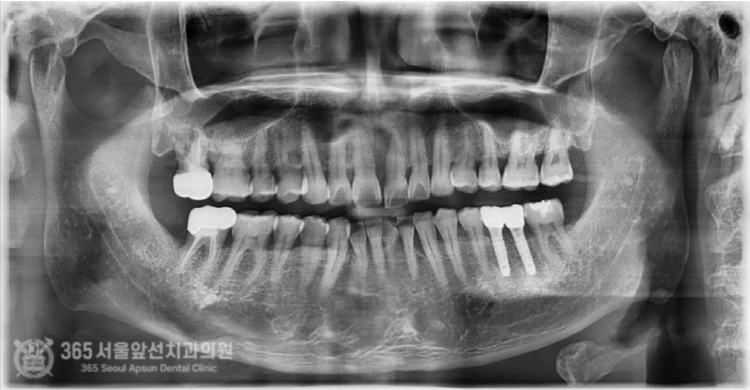

몸에서 냄새가 나고 고름이 나오다가 이제는 저절로 빠질 것 같아요... 안녕하세요. 도화역치과 365서울앞선치과의원입니다. 오늘은 심한 풍치를 앓던 앞니 임플란트 치료증례를 살펴보겠습니다. 이 환자분은 저와 특별한 사연이 있는 환자분이십니다. 바로 제가 일하던 치과의 소독실 전담 선생님의 남편분이신데요. 이렇게 가까이서 소통하던 직원분들도 가족의 치료를 믿고 맡겨주니 기대에 부응하기 위해 책임감을 막중히 느낍니다 ㅎㅎ 촬영일시 : 2024.07.02. 처음 내원당시 엑스레이 사진입니다. 왼쪽 앞니가 많이 안좋아 보입니다. 심한 풍치로 인해 잇몸뼈가 거의 다 없어졌고 치아가 저절로 빠질 정도로 흔들린다고 하셨습니다.

촬영일시 : 2024.07.02. 풍치로 인한 염증 부위를 색상으로 표시해보았습니다. (노란색) 3차원 CT를 이용하여 분석해보니 잇몸뼈가 염증으로 인해 녹은 상태로 매우 심각했습니다.....ㅠㅠ 촬영일시 : 2024.07.02. 결국 해당 치아는 발치를 하게 되었고, 임플란트 식립과 동시에 염증으로 인해 없어진 뼈를 재건하는 골이식을 시행하게 되었습니다. 발치를 하고 나서 임플란트 식립 및 골이식 수술 전 확인해보니 염증으로 소실된 뼈가 상당합니다. 촬영일시 : 2024.07.02. 임플란트를 식립했고 그 위로 두툼하게 골이식을 시행합니다. 일반적으로 골이식은 흡수되는 양이 상당합니다. 그래서 앞니 부위와 같이 미적으로 중요한 부위에서는 자연스러운 잇몸의 볼륨을 위해서 흡수되는 양을 감안하여 많은 양의 골이식을 시행하고있습니다. 임플란트를 식립 후에는 보통 작은 임시틀니를 드리고 그걸 사용하시는 경우가 많은데요. 지금처럼 골이식이 많이 들어간 경우에는 임시틀니를 사용할 경우 이식한 뼈가 제대로 성숙되지 못하는 경우가 많기에 다른 방식의 임시치아를 해드리고 있습니다. 위 환자분께서도 붙이는 형태의 임시치아를 해드렸고 잘사용하셨습니다. 촬영일시 : 2024.11.01. 4개월이 지나서 임플란트가 뼈와 잘 결합되었구요. 이식한 뼈도 단단해졌기에 슬슬 본 뜰 준비를 해봅니다. 동그랗게 회색 단추가 달려있는데요. 치유지대주라고 부르는 구조물로 이걸 이용하여 본을 뜨게 됩니다. 촬영일시 : 2024.11.05. 완성된 최종 보철물입니다. 사실 중간에 임플란트와 연결된 임시치아를 사용하여 잇몸 모양을 잡아주는 과정을 거쳤는데요. 아쉽게도 해당 과정에 대한 사진이 없군요 ㅠㅠ 이렇게 섬세하고 복잡한 과정을 거쳐서 임플란트 치료가 마무리 되었습니다 ㅎㅎ 이식된 뼈 부위도 통통하게 뼈가 잘되어있습니다 ㅎㅎ 만족스럽습니다. 촬영일시 : 2024.11.05. 치료가 마무리 된 후 엑스레이 사진입니다. 최종 보철물 장착 완료까지 자연스럽게 잘 마무리되어 기분이 좋네요. 직원분께서 가족의 치료를 믿고 맡겨주셨고, 그에 보답할 수 있어 기분 좋은 치료 증례였습니다. 앞으로도 더 유익한 치료 증례로 찾아뵙겠습니다. 도화역치과 365서울앞선치과의원이었습니다. 감사합니다. [ 치료기간: 2024년 7월2일 ~ 2024년 11월 5일 ] ※ 365서울앞선치과의원의 모든 포스팅은 각 진료과 의료진이 직접 작성합니다. 365서울앞선치과의원 블로그의 임상 케이스 게시물은 환자분께 의학적으로 정확하고 상세한 정보를 드리기 위해 각 진료과 의료진이 직접 작성하며, 모든 증례 사진은 본원 의료진이 직접 시술한 증례를 촬영한 것으로, 의료법 제23조, 제56조에 의거하며 환자분의 동의를 얻어 포스팅에 사용하였습니다. 또한 해당 케이스는 본 환자분의 치료 결과이며, 환자 상태에 따라 치료의 결과는 달라질 수 있습니다. |